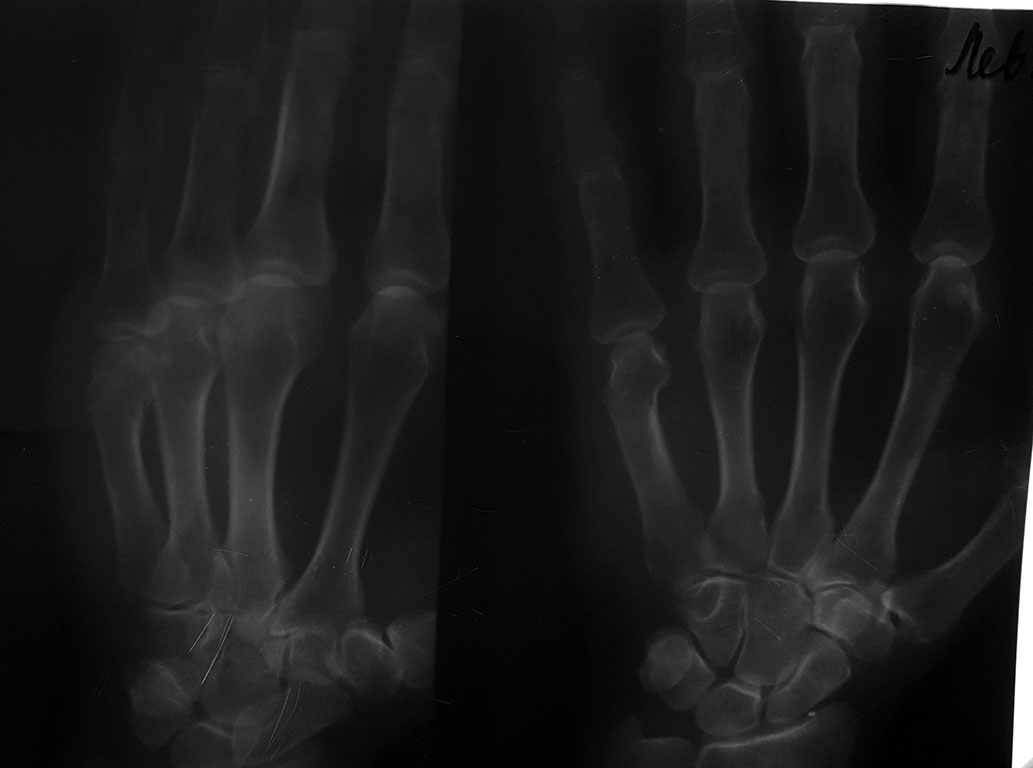

Поступила женщина 1949 г.р. Травма бытовая Перелом пятой пястной кости

Смещение под углом 10 градусов и по ширине 2мм. Тактика лечения вызвала

дискуссию в отделении  Показано ли в данном случае оперативное лечение

Просьба поделиться ссылками о допустимых смещениях при переломах пястных

костей